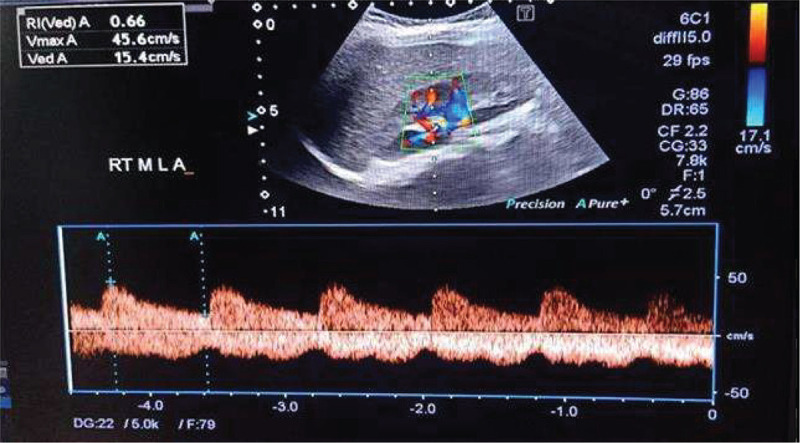

Background and aim: The aim of the current study is to assess the relation between carotid intima-media thickness (CIMT) measurements, renal Doppler resistive index (RI) and serum levels of interleukin-13 (IL-13) and annexin-V (An-V) in children with idiopathic nephrotic syndrome (INS).

Materials and methods: The present case-control study was conducted on 60 children with INS and 60 age- and sex-matched healthy children. All participants were subjected to evaluation of serum levels of IL-13 and An-V and ultrasound Doppler measurement of CIMT and renal RI.

Results: Patients expressed significantly higher An-V (5.9 ± 2.6 vs. 2.1 ± 0.8 ng/mL, p<0.001) and IL-13 (19.2 ± 7.6 vs. 3.4 ± 1.4 ng/L) levels when compared with healthy counterparts. Moreover, it was shown that patients had significantly higher CIMT (0.49 ± 0.06 vs. 0.35 ± 0.03, p<0.001) as compared to controls. No significant differences were noted between the studied groups regarding right or left RIs. Correlation analysis identified significant direct correlation between serum An-V levels and albumin/creatinine ratio (ACR) (r = 0.55), cholesterol (r = 0.48), triglycerides (r = 0.36), IL-13 (r = 0.92) and CIMT (r = 0.53). Similar correlations could be found between serum IL-13 levels and CIMT measurements and the corresponding parameters.